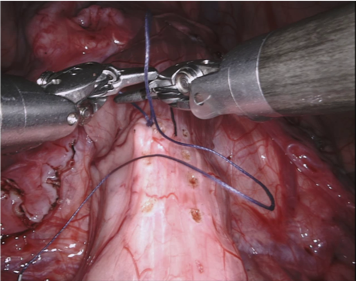

Our challenge was made up of 3 sub-problems. The first was binary instrument segmentation, where each frame was separated into da Vinci Xi instruments and a background class, which contained an ultrasound probe, surgical clips and porcine tissues. The second task was instrument part segmentation, where we scored the participants on whether they could correctly segment each articulating part of the instrument (see Fig. 3). Our final task was to segment and classify the instruments (see Fig. 4).

We provided the first 225 frames of 8 sequences as training data and kept the last 75 frames of those 8 sequences as test data. 2 of the full 300 frame sequences were kept as test sequences. Test labels were kept hidden from the participants. Our datasets contain 7 different robotic surgical instruments. The Large Needle Driver, Prograsp Forceps, Monopolar Curved Scissors, Cadiere Forceps, Bipolar Forceps, Vessel Sealer and additionally a drop-in ultrasound probe, which is typically held in the jaws of the Prograsp Forceps instrument. Samples from the training datasets are depicted in Fig. 2 and examples of the different instrument types are shown in Figure 3 and 4.

IV-D Type Segmentation

The final challenge was to identify each instrument type from the list of Large Needle Driver, Prograsp Forceps, Monopolar Curved Scissors, Vessel Sealer, Fenestrated Bipolar Forceps and Grasping Retractor (see Fig. 4). Only 6 teams participated in this challenge, due particularly to the significant increase in difficulty in recognizing many of the da Vinci instruments from one another.